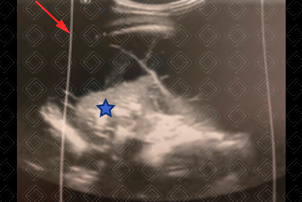

Texto alternativo para a imagem Figura 3. Créditos: Dra. Elazir Mota - Rio de Janeiro/RJ

Descrição das figuras 3 e 4: Ultrassonografia do hemitórax esquerdo evidenciando a consolidação homogênea com broncograma aéreo de permeio (asteriscos) e o derrame pleural (setas vermelhas). No caso do paciente em questão, trata-se de um derrame na fase fibrinopurulenta, pois observam-se alguns septos móveis no interior do derrame.

• Fase fibrinopurulenta (evolução de 2 a 10 dias): Caso a antibioticoterapia não seja adequada ou ineficaz, as bactérias que originaram a própria pneumonia tendem a invadir o líquido pleural e começam a acumular restos de células, leucócitos e bactérias. Inicia-se assim produção de fibrina, que acarreta no surgimento de septos, grumos e debris no interior do derrame pleural e na loculação. A loculação previne a disseminação do processo. Nesta fase, a abordagem cirúrgica se faz necessária para desfazer os septos e as lojas, permitindo a reexpansão adequada do pulmão;

• Ultrassonografia de tórax: Permite a graduação do derrame em leve, moderado ou acentuado e, além disso, auxilia na caracterização do derrame em exsudato, fase fibrinopurulenta ou organizada, ajudando na tomada de decisão pela equipe pediátrica e cirurgia pediátrica. Deste modo, é uma ferramenta auxiliar à radiografia do tórax na população pediátrica;